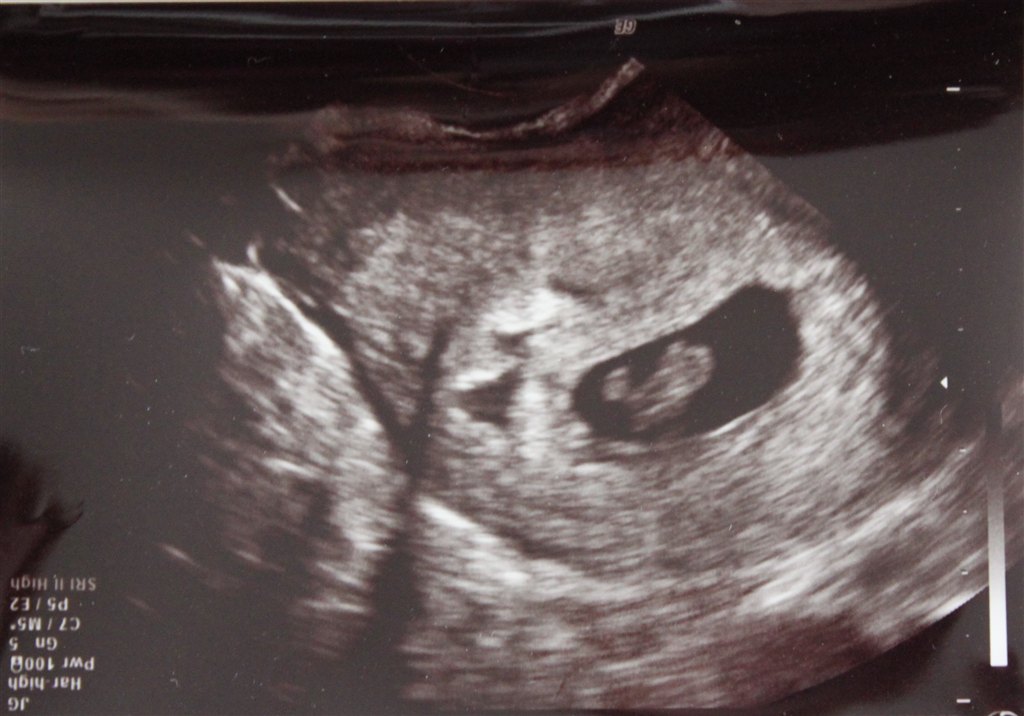

Jeg var til scanning, da jeg var 7+1 (se de vedhæftede billeder).

Den ene af mine havde gemt sig lidt, så den er lidt utydelig

Vedhæftede fotos (klik for at se i fuld størrelse)